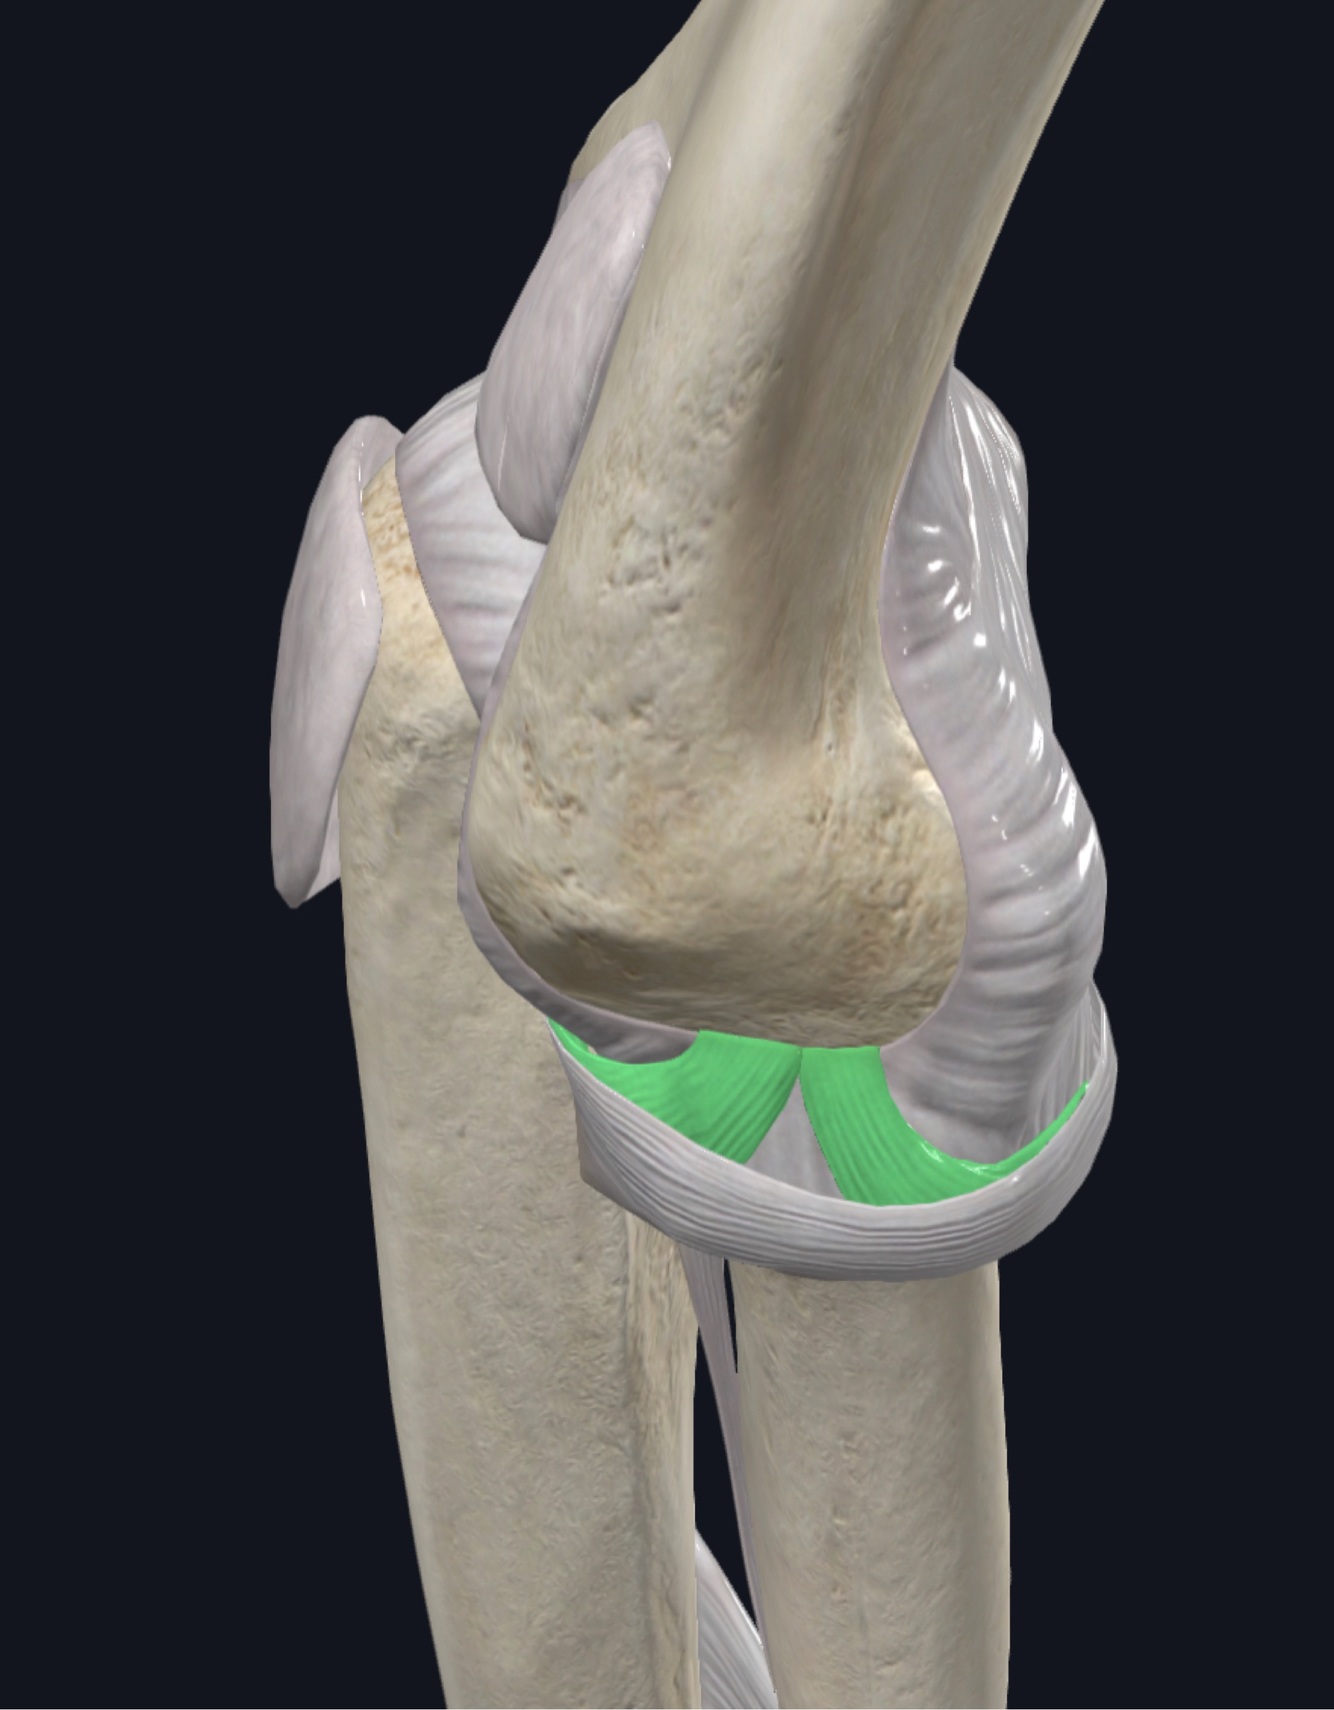

What is the bare area of the ulna?

Non-articular portion of the ulna between the olecranon articular facet and the coronoid articular facet. Located ~2cm from triceps insertion, between the tendons of FCU/ECU Important because you aim for there when doing olecranon osteotomies

What is the proximal ulnar dorsal angulation (PUDA)?

~5 degrees located ~5 cm distal to the tip of the olecranon Important because it is a landmark for comparing to the contralateral side in patients with comminuted or distorted anatomy